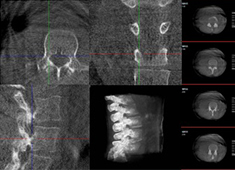

機器人做胸椎手術怎么樣:經(jīng)皮釘棒系統(tǒng)內(nèi)固定術案例分享

使用骨科手術機器人做胸椎手術的效果怎么樣?今天普愛醫(yī)療分享一則臨床案例——經(jīng)皮釘棒系統(tǒng)內(nèi)固定術,看看普愛手術機器人如何助力手術順利進行。...